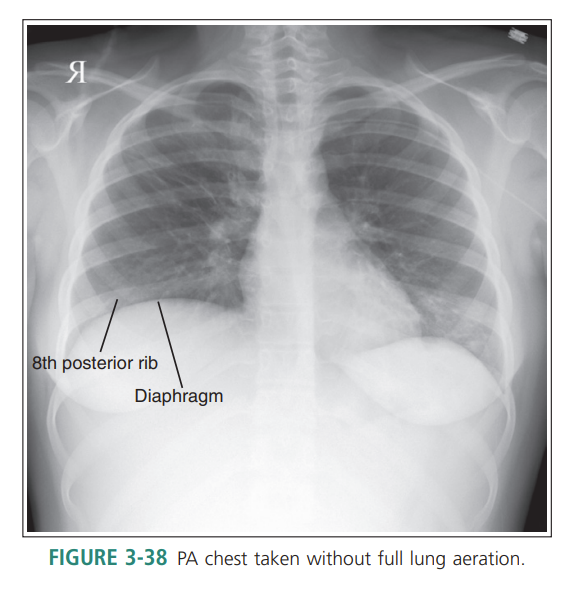

Inspiration did not occur, lungs are not filled with air

Lungs without full aeration